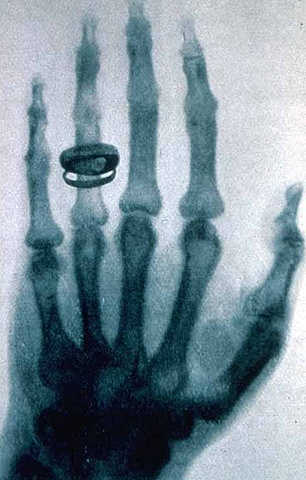

• Descubrimiento de los Rayos x

Descubrimiento de los Rayos x

Wilhem Conrad Roentgen descubre los rayos x, al desarrollar la primera radiografía de la historia en la mano de su esposa.